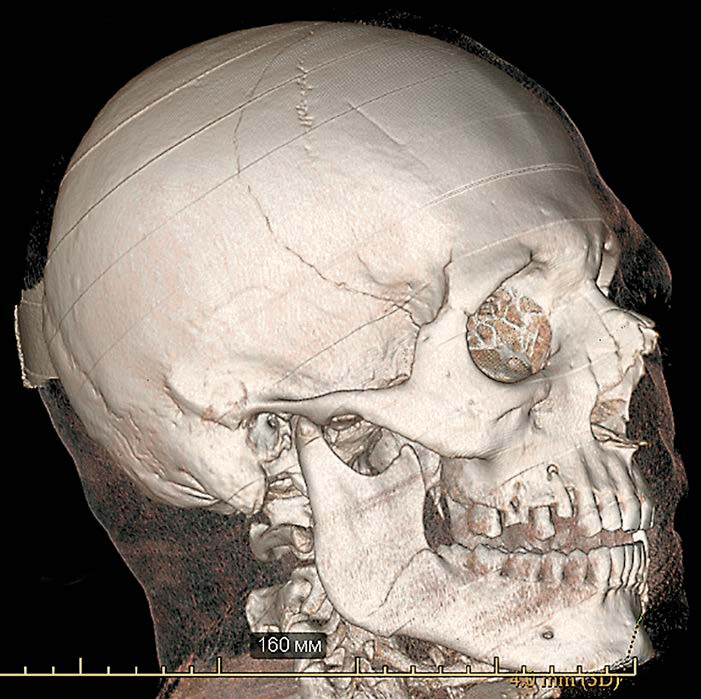

На снимке по МСКТ костей черепа в 3D-реконструкции определяются многооскольчатые переломы лобной кости, теменных костей